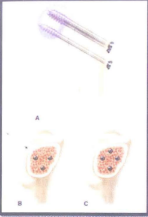

Hình 4.19. Hình ảnh X-quang sau mổ kết hợp xương vít xốp cổ xương đùi trái

1.3.2. Kỹ thuật kết hợp xương bằng vít cho gãy cổ xương đùi

- Đặt bệnh nhân trên bàn mổ, có sử dụng bàn chỉnh hình và chuẩn bị máy, màn tăng sáng C-arm.

- Dưới màn tăng sáng, kéo nắn chỉnh ổ gãy cổ xương đùi bằng bàn chỉnh hình đạt giải phẫu.

Hình 4.23. Các cách bắt vít xốp (S. Terry Canale – 2013) A. Phẫu thuật bắt vít xốp; B. Bắt vít xốp theo hình tam giác; C. Bắt vít xốp theo hình thoi.

- Rạch da nhỏ phía ngoài đùi tách các lớp cân và lớp cơ đến tận xương đùi.

- Dùng 01 đinh Kirschner khoan từ dưới mấu chuyển lớn xương đùi đến giữa chỏm xương đùi. Dùng màn tăng sáng để kiểm tra mũi khoan định hướng không bị lệch ra ngoài và không chạm vào mặt khớp, đi giữa cổ xương đùi.

- Làm tương tự đối với 02 kim Kirschner sau theo hình tam giác ngược hoặc 03 vít sau theo hình thoi như hình 4.23

- Dùng khoan vít rỗng lòng khoan đến đẩu mũi đinh Kirschner.

- Đo và bắt vít rỗng lòng theo đường vừa khoan

- Kiểm tra lại dưới màn tăng sáng để cổ xương đùi đạt giải phẫu, không có vít nào chạm vào mặt khớp và lệch hướng ra ngoài.

- Đóng vết mổ.